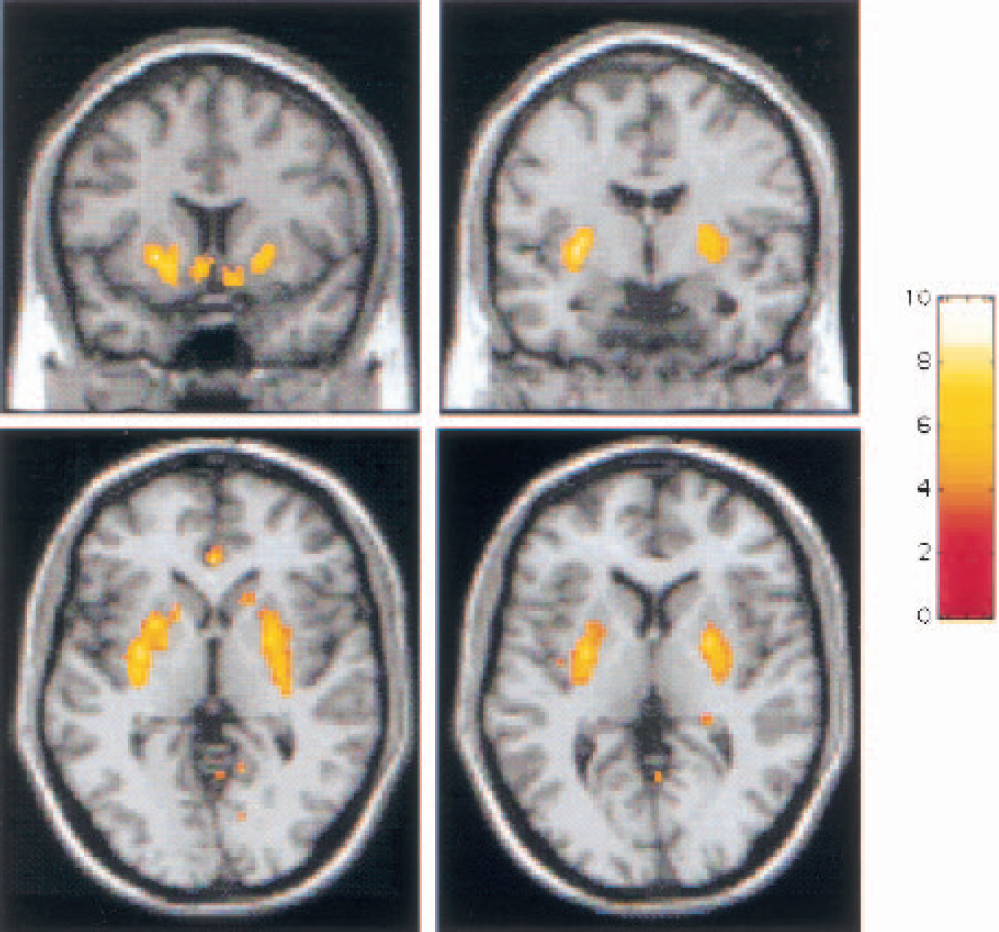

Of the four self-report items, only euphoria was significantly correlated with ΔV3″, such that a greater increase in euphoria was associated with higher [11C]raclopride displacement. This association was observed in the VST and SMST (Fig. 7), as well as at the level of the striatum as a whole (

Correlation between subjective report of amphetamine-induced euphoria and decrease in [11C]raclopride V3″ in the limbic striatum (LST;

No association was found between baseline V3″ and amphetamine-induced changes in euphoria in any subregion (VST: